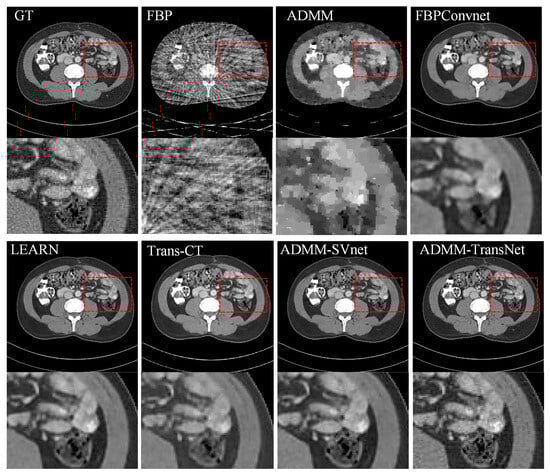

4.1. Simulation Data Research

| Views | 128 | 64 | 32 | ||||||

|---|---|---|---|---|---|---|---|---|---|

| Metric | PSNR | SSIM | MAE | PSNR | SSIM | MAE | PSNR | SSIM | MAE |

| FBP | 26.140 | 0.808 | 0.044 | 22.067 | 0.612 | 0.074 | 18.935 | 0.539 | 0.126 |

| ADMM | 33.751 | 0.929 | 0.021 | 30.883 | 0.915 | 0.027 | 29.753 | 0.907 | 0.038 |

| FBPConvNet | 39.854 | 0.952 | 0.020 | 34.243 | 0.938 | 0.028 | 30.648 | 0.916 | 0.035 |

| LEARN | 42.972 | 0.975 | 0.009 | 39.943 | 0.977 | 0.012 | 36.935 | 0.938 | 0.019 |

| Trans-CT | 40.877 | 0.966 | 0.011 | 35.855 | 0.941 | 0.019 | 32.430 | 0.922 | 0.023 |

| ADMM-SVnet | 43.229 | 0.995 | 0.007 | 42.974 | 0.989 | 0.008 | 40.212 | 0.972 | 0.013 |

| Ours | 44.633 | 0.996 | 0.006 | 43.726 | 0.992 | 0.007 | 42.036 | 0.979 | 0.011 |